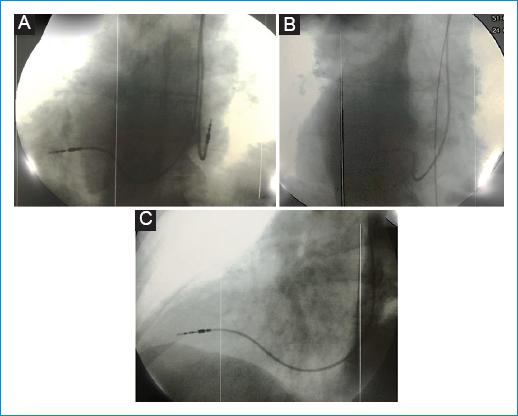

Teniendo en cuenta lo anterior, se consideró que la paciente cursaba con disfunción sinusal sintomática, por lo que se indicó el implante de marcapaso bicameral definitivo (previamente se descartaron causas reversibles de esta condición, como alteraciones electrolíticas o tiroideas). En el momento del implante se realizó venografía sin identificar alteraciones en el drenaje venoso; las punciones de la vena axilar fueron guiadas por marcas anatómicas, radiológicas y por venografía, sin complicaciones. Se avanzó el electrodo ventricular derecho (CapSureFix Novus MRI SureScan Leads 58 cm), se hicieron proyecciones RAO (oblicua anterior derecha) y LAO (oblicua anterior izquierda) teniendo en cuenta que las imágenes obtenidas son en espejo; por esta razón, se confirmó en RAO que el electrodo se dirigía al septum del ventrículo derecho, proyección contraria a la que se utiliza de forma usual (Fig. 1). Los parámetros de implante fueron onda R de 15 mV, impedancia de 518 ohm y umbral de 0,5 mV/04 ms. El electrodo auricular (CapSureFix Novus MRI SureScan Leads 52 cm) requirió reposicionamiento en tres ocasiones, pues en la posición usual la onda P registrada era menor de 1 mV, hacia septal presentaba una gran señal de campo lejano del ventrículo y la posición final óptima fue más lateral. Los parámetros de implante fueron onda P de 2,6 mV, impedancia de 536 ohm y umbral de 0,7 mV/04 ms; se conectaron electrodos al generador marca Medtronic (Advisa DR MRI), dejándose programado en modo MVP (Managed Ventricular Pacing).

Figura 1 Disposición de los electrodos durante el implante; imágenes de fluoroscopia. A: posición final de los electrodos. B: proyección RAO en donde se visualiza la dirección interventicular. Esta proyección normalmente se logra con LAO. C: proyección de LAO en donde se identifica la posición del electrodo en relación con el eje basal-ápex del VD. Esta proyección normalmente se logra con RAO en personas sin dextrocardia.LAO: oblicua interior izquierda; RAO: oblicua anterior derecha; VD: ventrículo derecho.